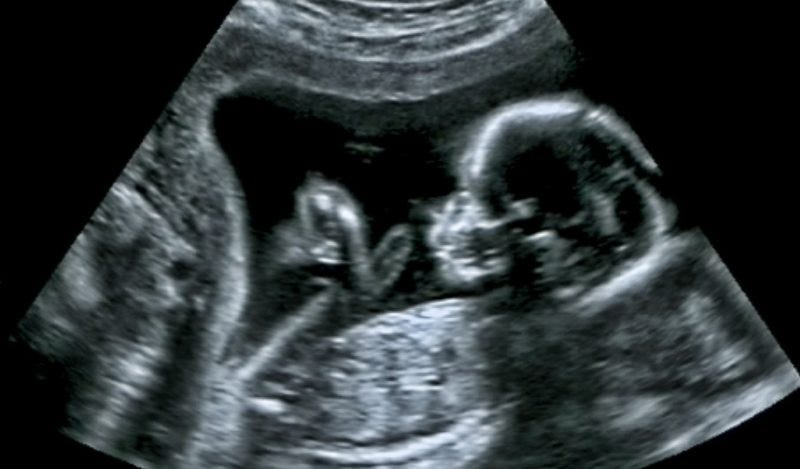

Pfizer recruited participants with an impeccable pregnancy history, and most were in their third trimester (27-34 weeks gestation), a stage when the baby’s major development has already occurred.

“It appears that they cherry picked the mothers to get the best results,” said Levi. “We have no idea what impact this vaccine has on the early stages of development of an embryo or foetus, because all the women had advanced pregnancies when they were recruited.”

“The first trimester is particularly vulnerable to adverse reproductive health outcomes,” she said.

“Based on only weak observational evidence, regulators have reassured the public that the vaccines are safe throughout pregnancy. However, we don’t have reliable evidence on the vaccine’s impact on miscarriages, malformation, foetal deaths, and maternal health risks because they excluded pregnant women from pivotal trials,” added Spelsberg.